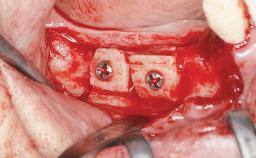

Replacement of Multiple Teeth in a Partially Dentate Posterior Mandible with a Fixed Dental Prosthesis Using a Flapless Approach

An 80-year-old female patient was referred to clinic for rehabilitation of her dentition. The patient’s medical history revealed no significant findings that would preclude routine dental and oral surgical procedures. She reported no drug allergies and was currently taking no prescription medications.

Her chief complaint was her inability to masticate efficiently due to the recent loss of her mandibular second premolars and first molars bilaterally. She expressed a desire for fixed prostheses in the shortest possible time due to her advanced age, requesting that replacement teeth should look as natural as possible. She was otherwise comfortable and not experiencing any symptoms from her teeth.